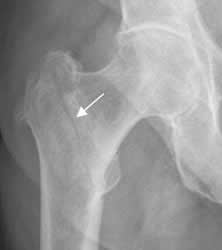

Fig 42. Angulación en varo.

Rx AP. Fractura subtrocantérica de la cabeza femoral, con desviación medial del fragmento distal.